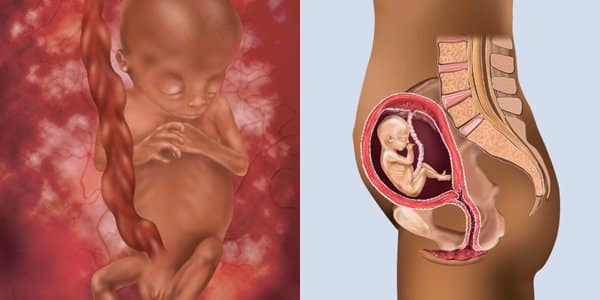

Этапы беременности: иллюстрации и развитие